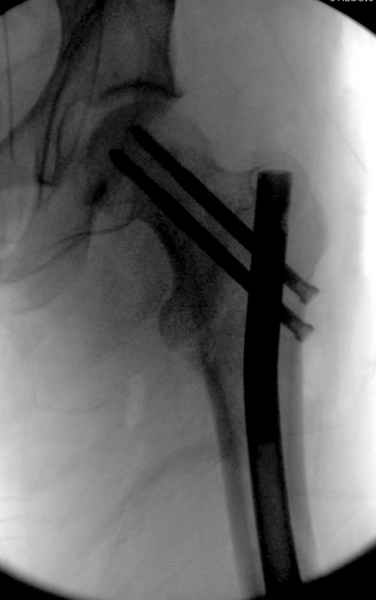

Как раз недавно у меня был примерный случай: больному 36 лет, поступил ночью, травма в результате мотоциклетной аварии, кроме чрезвертельного и спирального перелома левого бедра имеется переломы костей предплечья с этой же стороны. Скелетное вытяжение, а на следующий день больной про оперирован на ортопедическом столе с дистракцией. Чтобы не расколоть чрезвертельный перелом провели временную спицу ближе к переднему кортексу, из малого разреза костодержатель для репозиции, а фиксацию провели антиградным штифтом. Этапы операции на снимках.

Джолдас Кульджанов